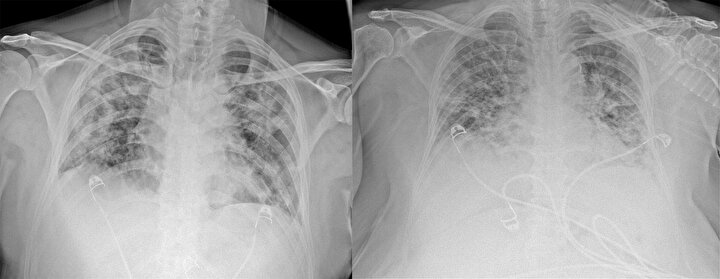

Ankara Şehir Hastanesinde koronavirüs tedavisi gören hastalara ait akciğer görüntüleri incelendi. Görüntülerde, hastalığın ne kadar hızlı ilerlediği ve akciğerleri nasıl tuttuğu ortaya çıktı.

Prof. Dr. Karalezli, koronavirüs tedavisi gören hastalara ait akciğer görüntülerinden hastalığın yol açtığı tahribatı ve hastalar üzerindeki etkileri anlattı.

Normal akciğer görüntüleri ile koronavirüs hastalarının akciğer görüntüleri arasında ciddi farklar bulunduğunu belirten Karalezli, şu bilgileri verdi:

"İnsanların aradaki farkları anlamaları için her iki akciğer görüntülerine de yer verdim. Görüntülerdeki beyazlıklar akciğerdeki tutulumu gösteren görüntüler ne yazık ki. Bu hastalar yoğun bakım hastaları. Filmler birbirine az çok benzeyen şekilde. Altta yatan hastalığı olanlarda ise daha kötü seyrediyor."